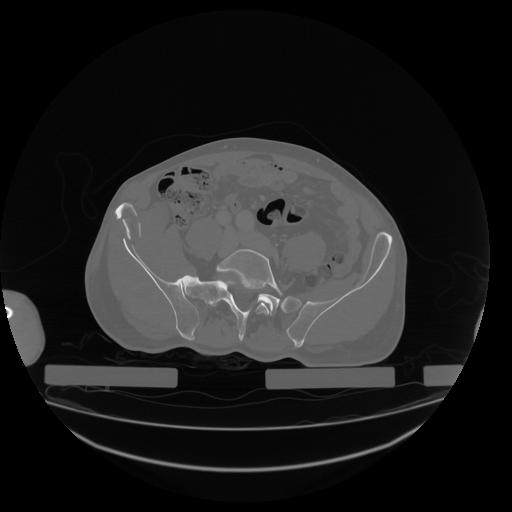

34 CUERPO,CE,Vol,1.0,CUERPO,,